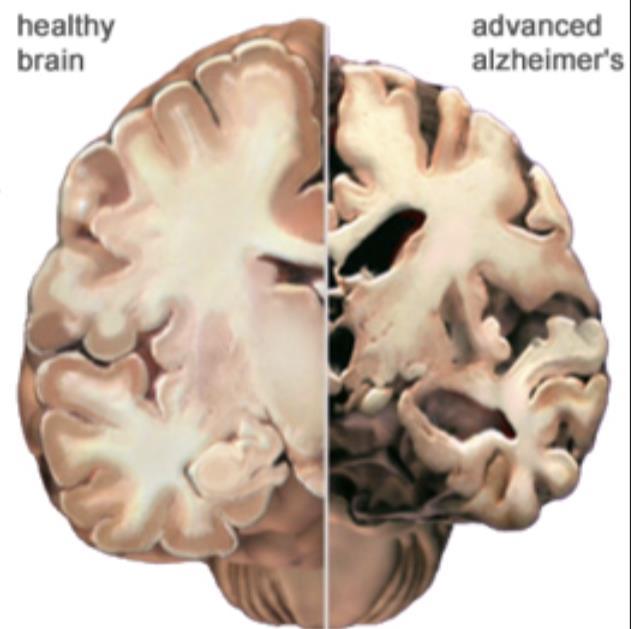

Dementia is the most common of the so-called neurodegenerative brain diseases (others include Parkinson’s disease and ALS/Lou Gehrig’s disease)

The most common type of dementia is Alzheimer’s disease

Dementia is the most common neurodegenerative brain disease